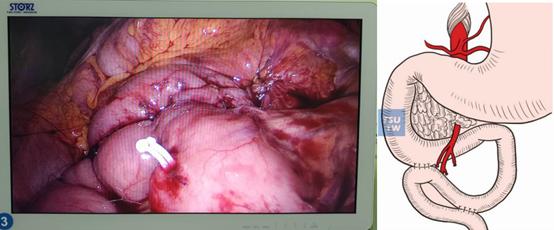

在科副主任張祖案帶領(lǐng)下,林常平副主任醫(yī)師、李振派副主任醫(yī)師及謝禮鋒主治醫(yī)師組成的醫(yī)生團(tuán)隊(duì),通過(guò)精心準(zhǔn)備和周密規(guī)劃,查閱國(guó)內(nèi)外相關(guān)手術(shù)資料及文獻(xiàn),申請(qǐng)心臟外科、麻醉科、泌尿外科及重癥醫(yī)學(xué)科等相關(guān)專業(yè)科室進(jìn)行術(shù)前會(huì)診MDT討論后,決定為林女士實(shí)施腹腔鏡十二指腸空腸吻合+空腸空腸吻合術(shù)。在江長(zhǎng)城、楊少輝麻醉醫(yī)師,陳莉莉護(hù)士以及張祖案團(tuán)隊(duì)的默契配合下,手術(shù)順利完成,僅用時(shí)50分鐘。